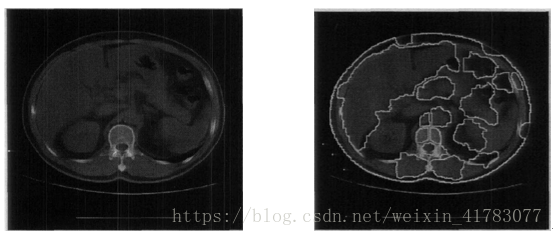

图7(a)是一幅原始肝脏CT图像,图7(b)是基于小波变换后的叠加了分割线的分割结果。从结果中可以看出,肝脏左叶也被成功地划进了肝脏的区域,该结果同样受到了“体效应”的影响,部分胃部的气泡也被划进了肝脏的区域,但所得结果还是可以接受的。

(a)肝脏CT图像 (b)分割结果

图7 基于小波变换的图像分割